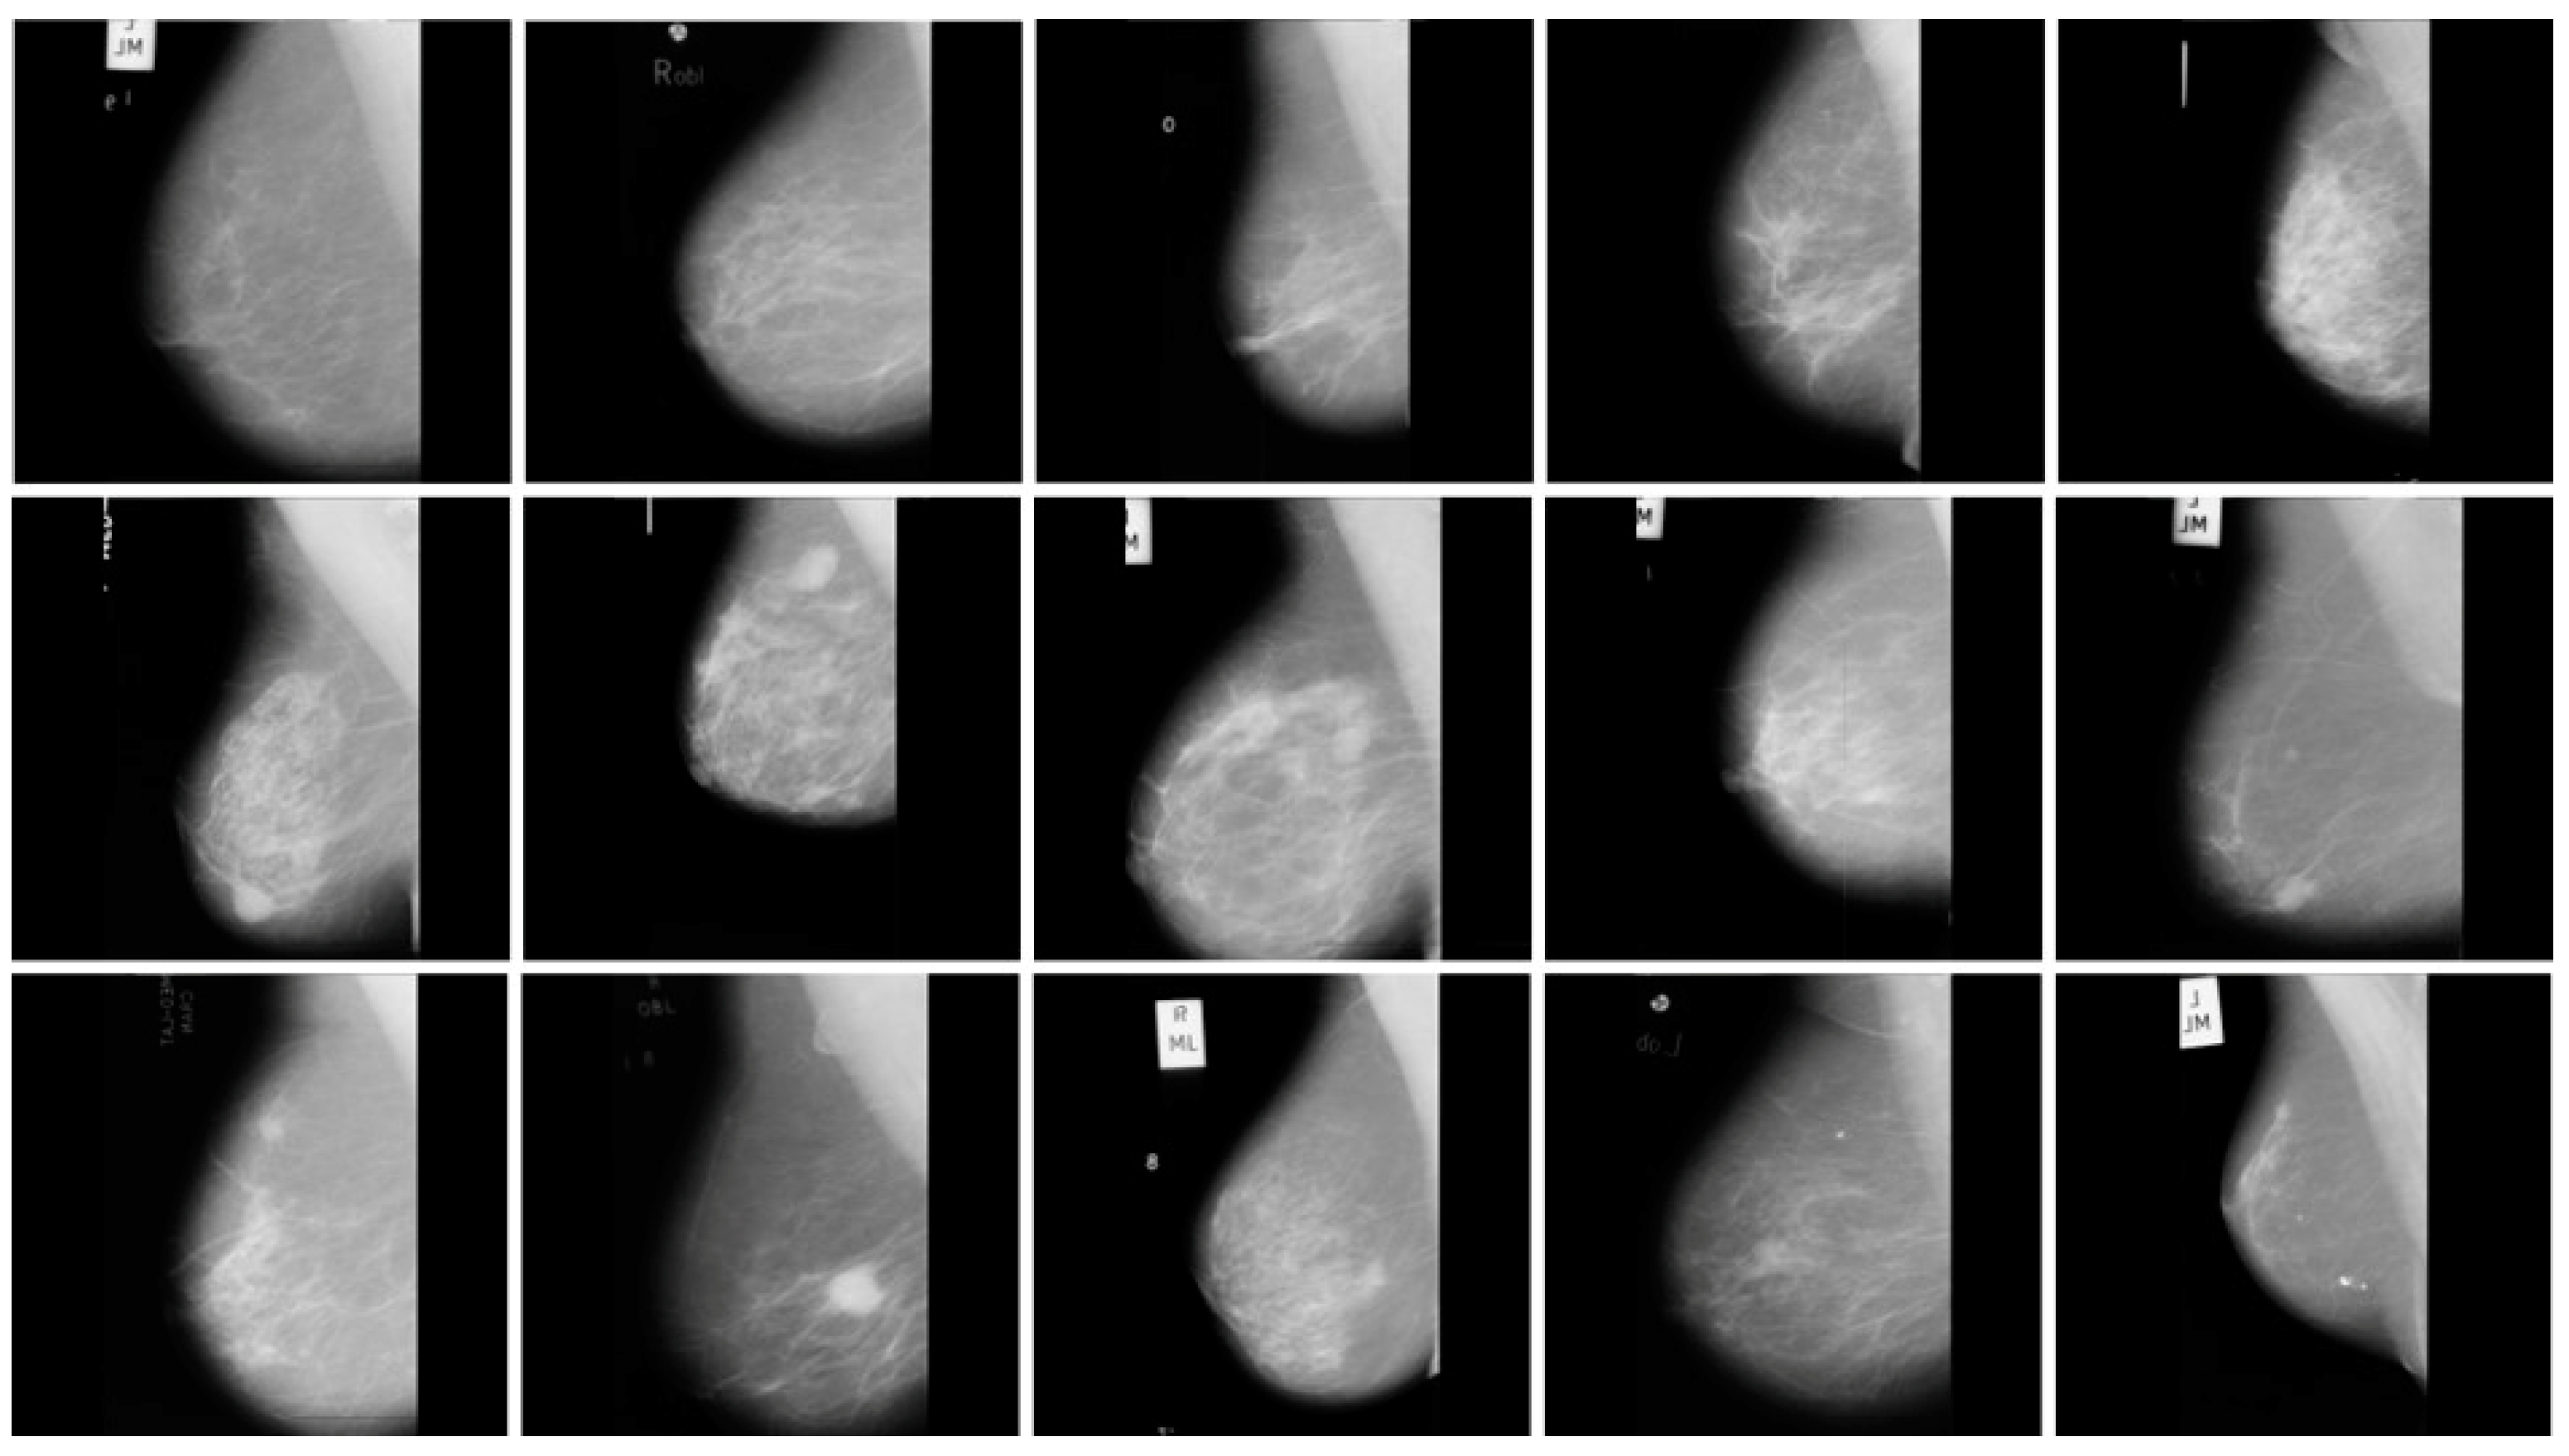

In this work, we used two publicly available benchmarks, including DDSM and MIAS. The DDSM was taken from the University of South Florida, maintaining the accessibility of the dataset on the web. The dataset contains 55,890 total images and includes three different classes, for instance benign, malignant, and normal, as shown in Figure 5. For the experimental results, we utilized a small version of the DDSM [40] for classification. Similarly, the MIAS [40] dataset contains three different classes, including normal, benign, and malignant, where it contains 209, 62, and 51 numbers of images for each class, respectively. This dataset also represents details for ground-truth information in the mammogram images, for instance, abnormality center coordinates, background tissue, tumor type, and approximate radius for enclosing the abnormality circle. The visualization samples of the MIAS datasets are presented in Figure 6. In the training phase, we utilized both datasets with a ratio of 70% for training, 20% for validation, and 10% for testing.

Figure 6.

Sample images from MIAS dataset.